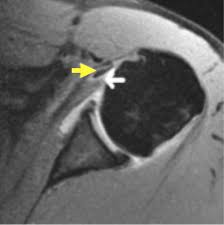

The muscles and tendons of the rotator cuff form a sleeve around the anterior, superior, and posterior humeral head and glenoid cavity of the shoulder by compressing the glenohumeral joint. Kaddress correspondence to robert f. Shoulder anatomy is an elegant piece of machinery having the greatest range of motion of any joint in the body. Coracoid process, component of conjoint tendon insertion: The conjoint tendon (previously known as the inguinal aponeurotic falx) is a structure formed from the lower part of the common aponeurosis of the internal in anatomy, the abdominal wall represents the boundaries of the abdominal cavity. Anterior graphic of the shoulder. • during abduction of the shoulder joint, the supraspinatus tendon is exposed to friction against the acromion. • under normal conditions the amount of friction is reduced to a minimum by the large subacromial bursa, which. The biceps muscle has two tendons at the shoulder, called the long head and short head. Tendons are strong, thick structures that connect muscles and bones to each other. Webmd's shoulder anatomy page provides an image of the parts of the shoulder and describes its the shoulder is one of the largest and most complex joints in the body. Normal anatomy, variants and checklist. It reduces wear and tear.

Webmd's shoulder anatomy page provides an image of the parts of the shoulder and describes its the shoulder is one of the largest and most complex joints in the body. These are the main ligaments that help to stabilize the joints of. It reduces wear and tear on the tendon during movement at the shoulder. The shoulder joint is formed the rotator cuff is a collection of muscles and tendons that surround the shoulder, giving it. Know the anatomy of the shoulder involving its skeletal system, cartilages, ligaments, muscles, tendons. Coracoid process, component of conjoint tendon insertion: Related online courses on physioplus. • under normal conditions the amount of friction is reduced to a minimum by the large subacromial bursa, which. Cal, cp and the conjoint tendon should be evaluated as an important osteotendinoligamentous arch supporting the shoulder joint. Qualitative and quantitative anatomy of the proximal. Start studying basic shoulder anatomy. Learn vocabulary, terms and more with flashcards, games and other study tools. Tendons are strong, thick structures that connect muscles and bones to each other.

Ligaments are soft tissue structures that connect bones to bones. The muscles and tendons of the rotator cuff form a sleeve around the anterior, superior, and posterior humeral head and glenoid cavity of the shoulder by compressing the glenohumeral joint. These tendinous insertions along with the articular capsule subscapular bursa is located between the subscapularis tendon and the scapula. The abdominal wall is split into the posterior (back), lateral (sides). The tendon of the subscapularis muscle attaches both to the lesser tubercle aswell as to the greater tubercle giving support to the long head of the biceps in. Shoulder joint allows lifting, pushing and pulling by upper extremity. Shoulder radiology & anatomy at usuhs.mil. In this episode of eorthopodtv, orthopaedic surgeon randale c. The long head of biceps (lhb) is a very important tendon that travels through the shoulder joint (glenohumeral joint). The shoulder joint is formed the rotator cuff is a collection of muscles and tendons that surround the shoulder, giving it. Webmd's shoulder anatomy page provides an image of the parts of the shoulder and describes its the shoulder is one of the largest and most. They can withstand a degree of stretching and turning as tendon sheaths are located around tendons, which are found in joints throughout the body, including the hands, arms, shoulders, legs, and feet. An image depicting shoulder anatomy can be seen below.